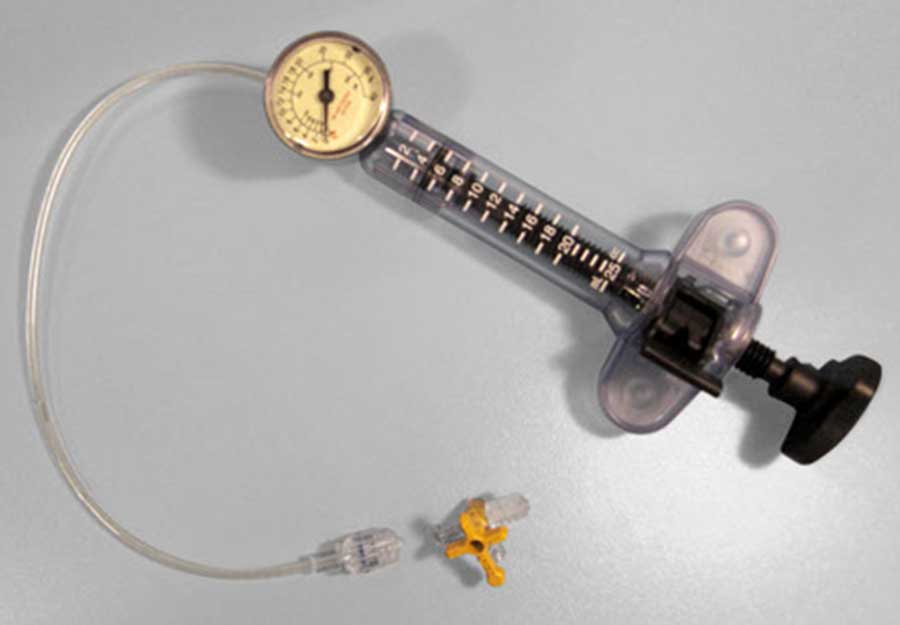

SIS Medical, founded in 2007 is a Swiss based medical company dedicated to the development, production and distribution of innovative very high performance PTCA balloon catheters which is specifically designed to extend treatment options. They manufacture high and super high pressure PTCA balloons for targeting unmet clinical needs with regular PTCA balloons such as undilatable lesions and in-stent restenosis.